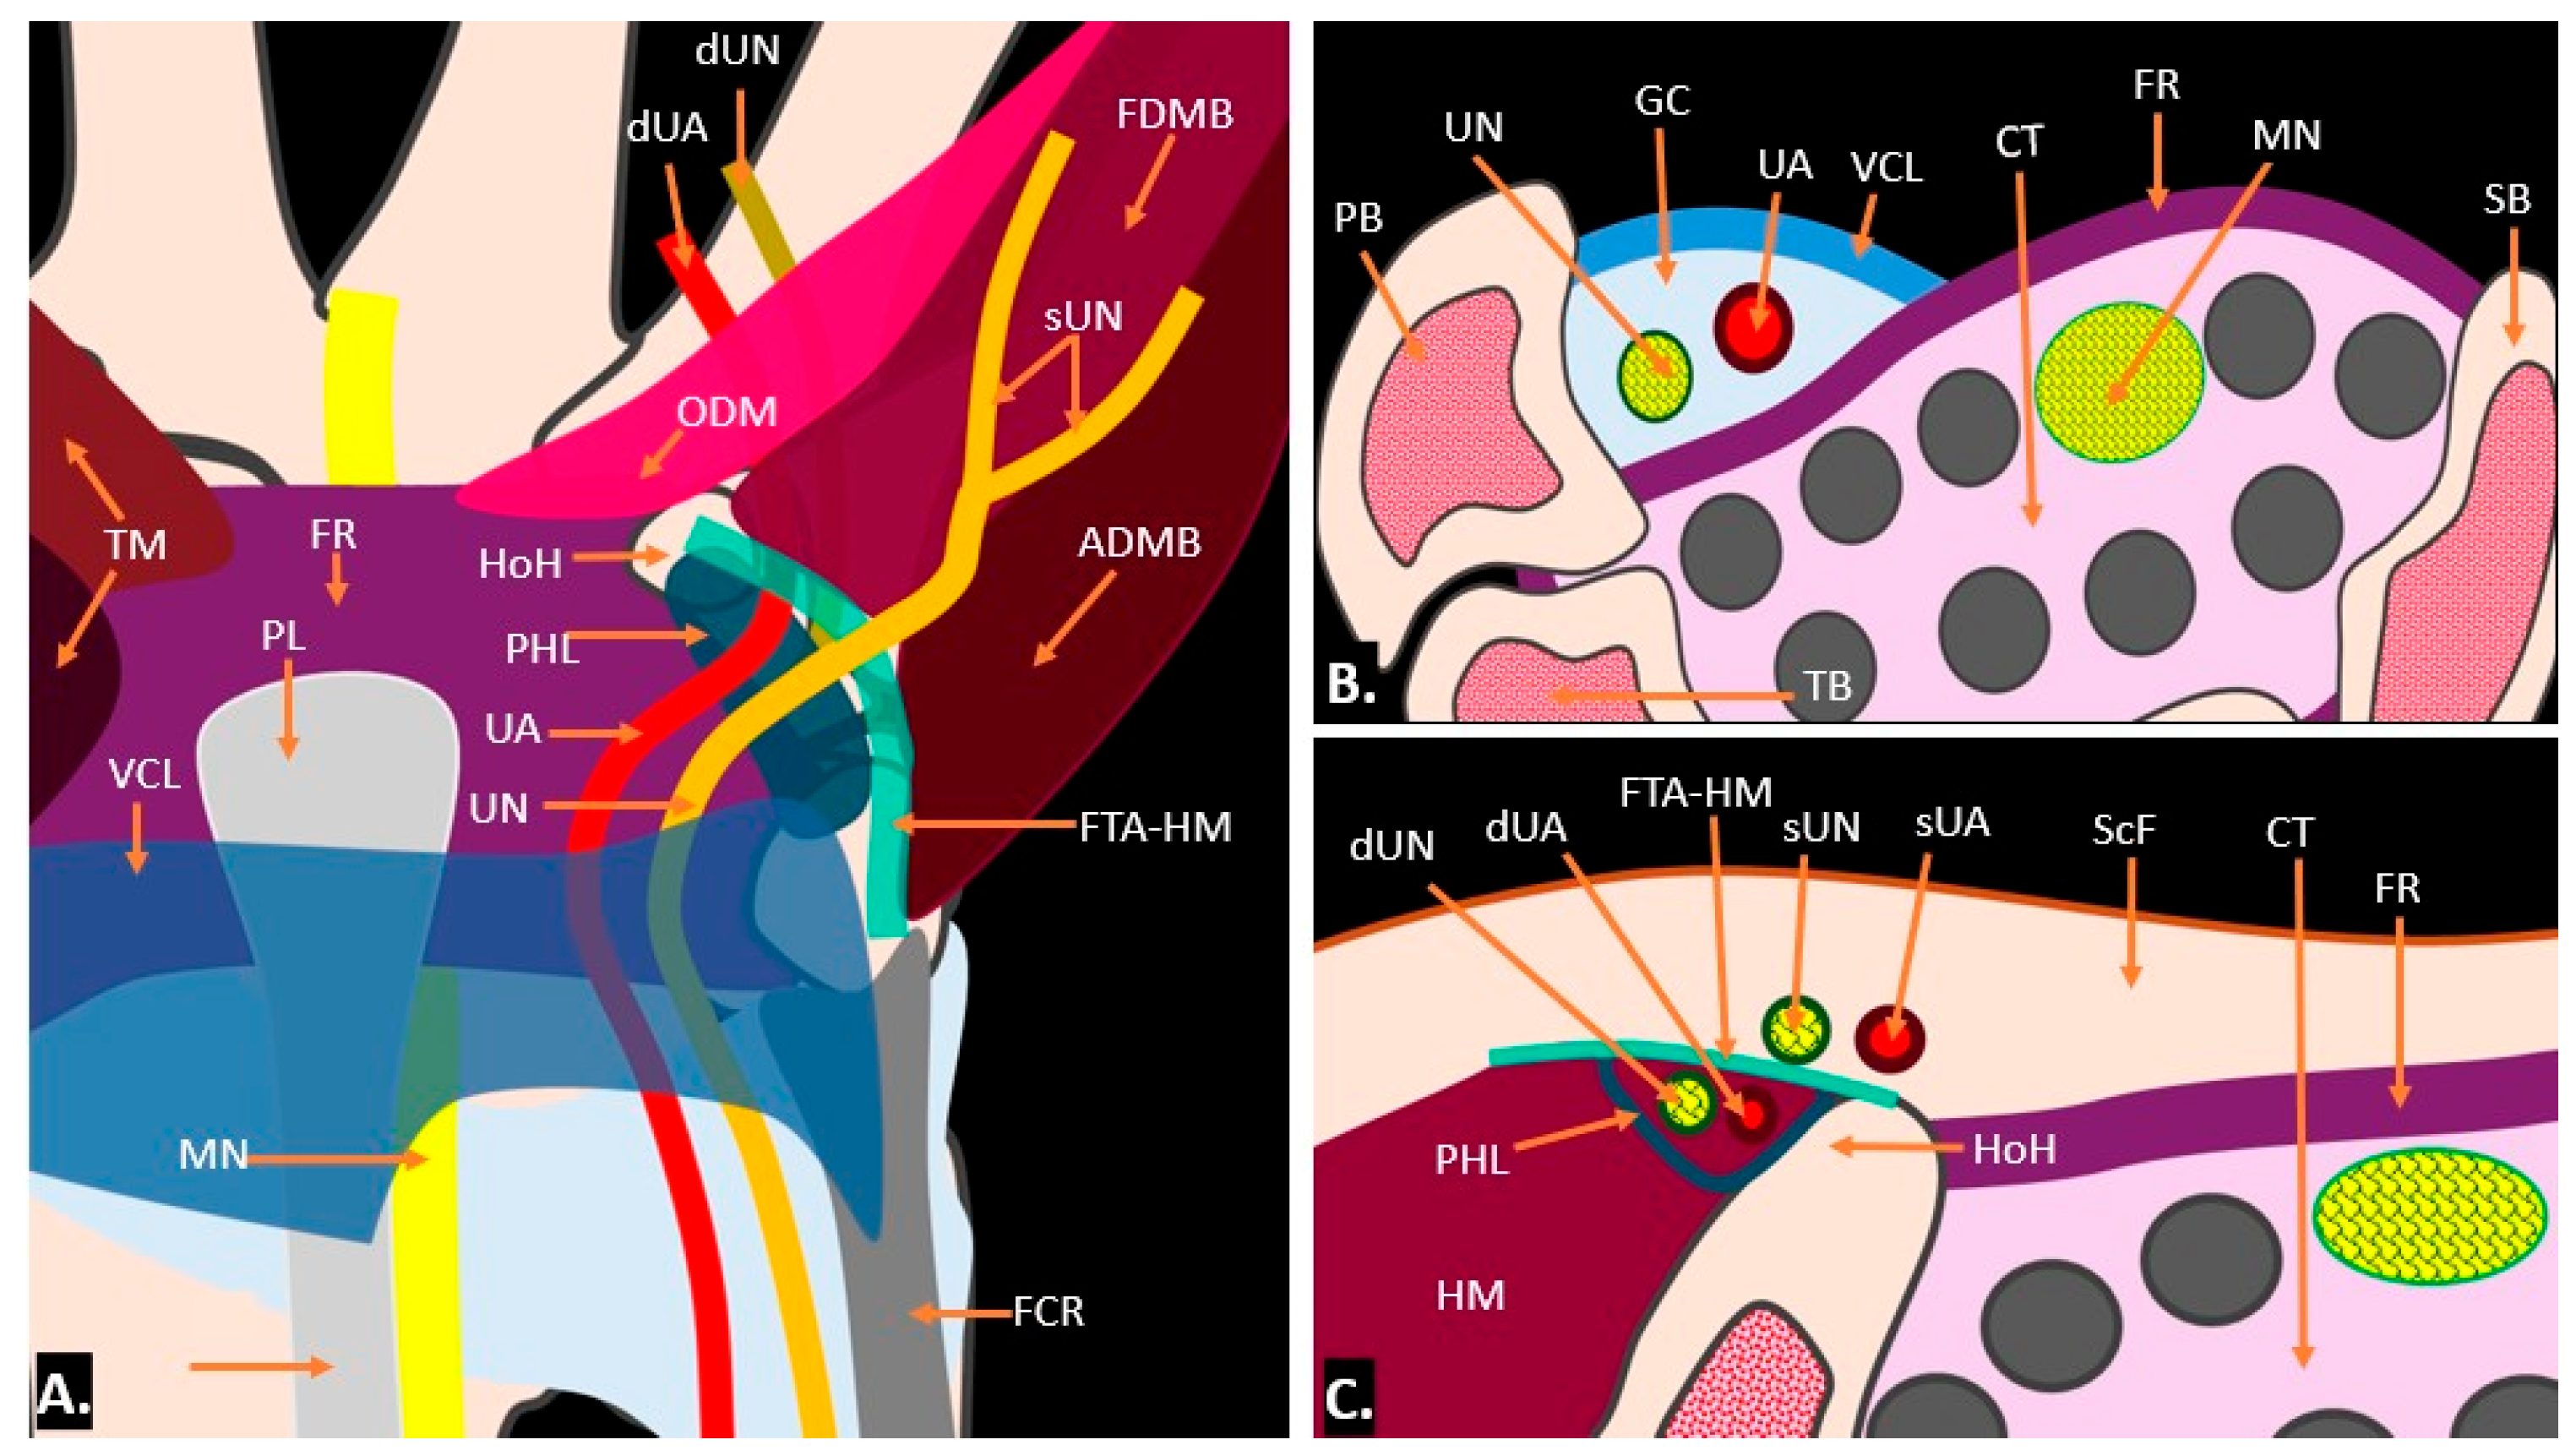

2. Clinical Anatomy

3.1. Ultrasound Technique and Anatomy